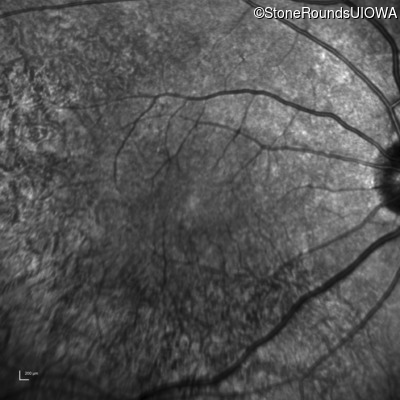

Infrared Fundus Photograph - Right - 20/20

Exemplar